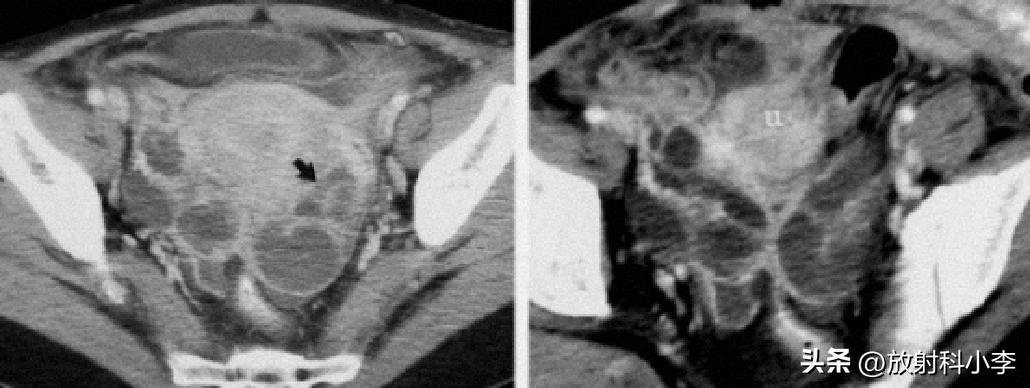

A,B.平扫CT示子宫腔内低密度灶,双侧宫旁间包块,呈囊实性改变;C,D.增强CT示宫腔内肿块强化程度低于子宫肌层;双侧宫旁病变多囊状改变,囊壁较厚,与周围组织结构分界不清。

术后诊断:子宫内膜癌,及双侧卵巢输卵管脓肿